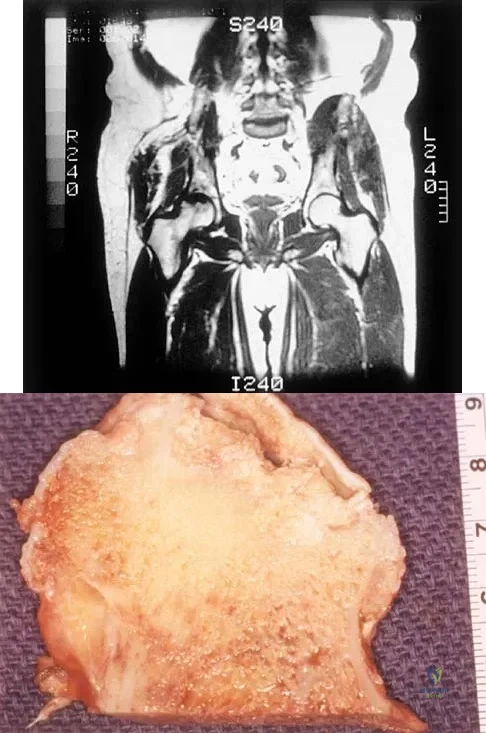

A 35-year-old patient has right hip pain. Figures 34a and 34b show the coronal MRI scan and the biopsy specimen. What is the most likely diagnosis?

Explanation